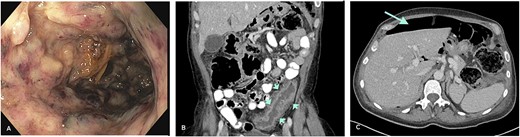

A sigmoidoscopy revealed severe inflammation with deep ulcers and patches of mucosal necrosis (Fig. 1A). Biopsies from the rectum and distal colon showed severe inflammation and necrosis, and immunohistochemistry (IHC) for CMV was negative. Treatment was changed to intravenous methylprednisolone 50 mg/day and metronidazole/ciprofloxacin. An abdominal computed tomography (CT) scan revealed a left-sided colonic wall thickening with free intra-abdominal air (Fig. 1B and C). Emergency laparoscopy showed purulent peritonitis with a perforation of the descending colon. Due to the lack of inflammation of the right colon and according to the patient’s preference to avoid subtotal colectomy, a laparoscopic left hemicolectomy with formation of an end colostomy (Hartmann’s procedure) was performed. Postoperatively, the patient’s condition improved rapidly. Biologic therapy with infliximab was started 2 days after surgery to address the severe proctitis and potential inflammation in the remnant colon. Gross specimen examination showed a severe diffuse necrotizing colitis, and histology revealed an extensive ulcerating colitis with pseudomembranous character with patchy, transmural necrosis and perforation in the proximal descending colon (Fig. 2A, B1 and C1). The mucosal inflammation ended abruptly adjacent to the perforation, and the oral resection margin showed normal mucosa, whereas the aboral margin was heavily inflamed and partially necrotic.

(A) Severe colitis with deep ulcerations on endoscopy. (B) Left-sided colonic wall thickening (CT-scan; short arrows). (C) Intraperitoneal air indicative of hollow viscus perforation (CT-scan; long arrow).

The specimen shows severe diffuse necrotizing colitis (A). Histology reveals extensive ulcerous colitis with deep-reaching ulcers and mural necrosis (B1 and C1). Multinucleated epithelial cells with eosinophilic inclusions can be discerned (insert B1). Immunohistochemistry for human HSV confirms a widespread infection of the mucosa and the mural part of the colonic wall (B2 and C2). Epithelial cells, as well as stromal cells, are positive (insert B2). B1 and C1: Hematoxylin and Eosin; C1 and C2: Immunohistochemistry for HSV (Chromogen: Fast Red).

In the further workup, serologic tests were positive for HSV-1 + 2 immunoglobulin G and M, and a liver biopsy showed HSV hepatitis. HSV viremia with 60 million copies/ml was detected, suggesting a systemic herpes virus infection. Clinical examination revealed erosive genital lesions positive for HSV-2. IHC of the colonic specimen was performed and confirmed HSV infection in the ulcers and necrotic areas (Fig. 2B2 and C2). Further molecular analysis of the colonic tissue by type-specific PCR revealed HSV-2.